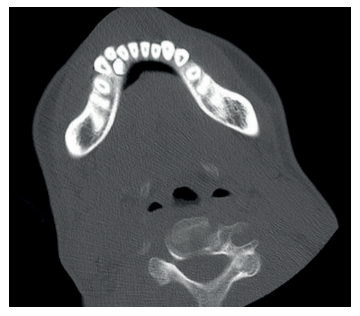

Los casos de osteonecrosis mandibular son frecuentes en pacientes con MPS tipo III y en algunos de los casos el diagnóstico se realiza en fases avanzadas por CBTC rutinarios, como mencionan Koehne y cols.30.

Cuando comienzan el recambio dentario, se debe mantener continuas revisiones odontológicas, puesto que en estos casos existen problemas para la exfoliación de los dientes deciduos. Se pueden encontrar dientes supernumerarios e inclusiones dentarias, que serán extraídos por un especialista en quirófano bajo sedación profunda, debido a la alteración cognoscitiva importante que suelen presentar y/o hiperactividad en fases intermitentes39 (Figuras 9, 10 y 11).

En los casos más avanzados resulta muy complicado realizar la exploración radiológica de manera convencional, por lo que se puede optar por TC, donde el paciente es acomodado utilizando posicionadores específicos, e incluso proceder a la sedación en ámbito hospitalario.